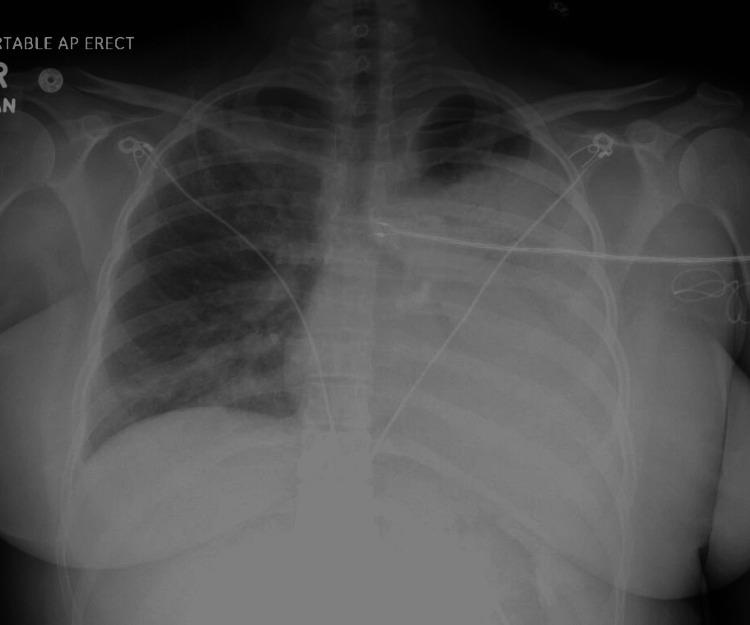

A twenty-two-year-old woman with a history of pediatric autoimmune neuropsychiatric disorders associated with streptococcal infection (PANDAS) on rituximab presented with fever, abdominal pain, and worsening shortness of breath requiring supplemental oxygen via nasal cannula one month after a severe acute respiratory syndrome coronavirus 2 (SARS-CoV2) infection from which she was minimally symptomatic and had recovered. Radiographic studies revealed bilateral patchy consolidations interspersed with ground-glass opacities (GGO). She was started on antibiotics for presumed community-acquired pneumonia with no improvement. Echocardiography revealed preserved biventricular function and a suspected intracardiac mass. A cardiac magnetic resonance imaging (CMRI) revealed myocarditis and no intracardiac mass. Fever persisted and oxygen requirements increased from FiO2 0.4 to 1.0. Repeat CXR showed subtotal left hemithorax opacification. Bronchoscopic samples showed a negative Gram stain and an unremarkable cell count differential. In view of this and given her lack of response to antibiotics with worsening respiratory status, high-dose steroids were started. She improved rapidly, and six days later she was off oxygen. Transbronchial biopsies showed benign parenchyma with some intra-alveolar fibrin deposition with no definitive evidence of viral cytopathic effect, vasculitis, or diffuse alveolar damage (DAD). Follow-up imaging in the pulmonary clinic revealed improvement of prior airspace disease with some new migratory opacities that completely resolved after 12 weeks. Pulmonary function tests and repeat CMRI were normal three months after discharge. Multisystem inflammatory syndrome in adults (MISA), post-covid organizing pneumonia (OP), and immune reconstitution inflammatory syndrome (IRIS) are rare and potentially steroid-responsive causes of pneumonia, which were in our differential diagnosis. It is imperative to consider the rare possibility of steroid-responsive pneumonia-like MISA, post-COVID-OP, and IRIS in patients with worsening respiratory symptoms following a recent SARS-CoV 2 infection.

一名22岁有儿童自身免疫性神经精神障碍伴链球菌感染(PANDAS)病史且正在接受利妥昔单抗治疗的女性,在感染严重急性呼吸综合征冠状病毒2(SARS-CoV2)后一个月出现发热、腹痛,呼吸急促加重,需要通过鼻导管吸氧,此次感染她症状轻微且已康复。影像学检查显示双侧斑片状实变,其间散在磨玻璃影(GGO)。考虑为社区获得性肺炎,她开始使用抗生素治疗,但病情无改善。超声心动图显示双心室功能正常,疑似心内肿物。心脏磁共振成像(CMRI)显示为心肌炎,无心内肿物。发热持续,氧需求从FiO2 0.4增加到1.0。复查胸部X线显示左半胸大部分致密影。支气管镜检查样本革兰染色阴性,细胞计数分类无异常。鉴于此,且考虑到她对抗生素治疗无反应且呼吸状况恶化,开始使用大剂量类固醇。她迅速好转,6天后不再需要吸氧。经支气管活检显示良性实质,有一些肺泡内纤维蛋白沉积,无病毒细胞病变效应、血管炎或弥漫性肺泡损伤(DAD)的确切证据。肺部门诊的随访影像学检查显示先前的气腔病变有所改善,出现一些新的游走性致密影,12周后完全消失。出院3个月后肺功能测试和复查CMRI均正常。成人多系统炎症综合征(MISA)、新冠后机化性肺炎(OP)和免疫重建炎症综合征(IRIS)是罕见的、可能对类固醇有反应的肺炎病因,均在我们的鉴别诊断范围内。对于近期SARS-CoV 2感染后出现呼吸症状恶化的患者,必须考虑类固醇反应性肺炎样MISA、新冠后OP和IRIS等罕见可能性。